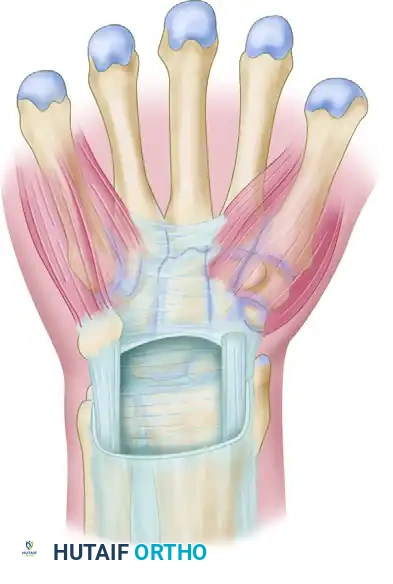

Surgical Techniques: Carpal Tunnel Release

Whether utilizing a standard open approach, a limited-incision technique, or an endoscopic method, the fundamental objective remains identical: complete division of the transverse carpal ligament under direct or endoscopic visualization.

Incision Planning and Approaches

The Standard Open Approach:

The traditional open technique provides unparalleled exposure. A longitudinal incision is made in the palm, typically starting just distal to the proximal palmar crease and extending proximally in line with the radial border of the ring finger (Kaplan's cardinal line). This axis safely parallels the median nerve while avoiding the palmar cutaneous branch, which lies more radially.

Limited and Minimal Incision Approaches:

Limited approaches, such as the "double incision" of Wilson or the "minimal incision" of Bromley, aim to reduce postoperative pillar pain and accelerate recovery, offering benefits similar to endoscopic techniques.

The use of specialized instruments like the "carpal tunnel tome" through a small palmar incision minimizes soft tissue trauma while providing adequate exposure.

Step-by-Step Surgical Execution

- Positioning and Anesthesia: The patient is positioned supine with the arm extended on a hand table. The procedure is typically performed under local anesthesia (WALANT - Wide Awake Local Anesthesia No Tourniquet) or regional block with a proximal pneumatic tourniquet.

- Incision and Superficial Dissection: The skin and subcutaneous tissues are incised. The palmar aponeurosis is identified and longitudinally divided.

- Identification of the Transverse Carpal Ligament: Blunt retractors are placed to expose the transverse fibers of the flexor retinaculum.

- Ligamentous Release: The ligament is carefully incised longitudinally, typically starting proximally and extending distally.

> Regardless of the technique selected, all structures to be incised must be clearly seen and identified. The safety of the median nerve must be visually verified before the final release of the transverse carpal ligament. Blind cutting is strictly contraindicated due to the risk of lacerating the median nerve, the recurrent motor branch, or the superficial palmar arch. - Exploration and Decompression: Once the ligament is divided, the median nerve is inspected for areas of pseudoneuroma or hourglass constriction. The canal is swept with a blunt dissector to ensure no distal fascial bands remain.

- Closure: The tourniquet is deflated, and meticulous hemostasis is achieved. Only the skin is closed; the flexor retinaculum is left open to allow for volumetric expansion of the carpal canal.